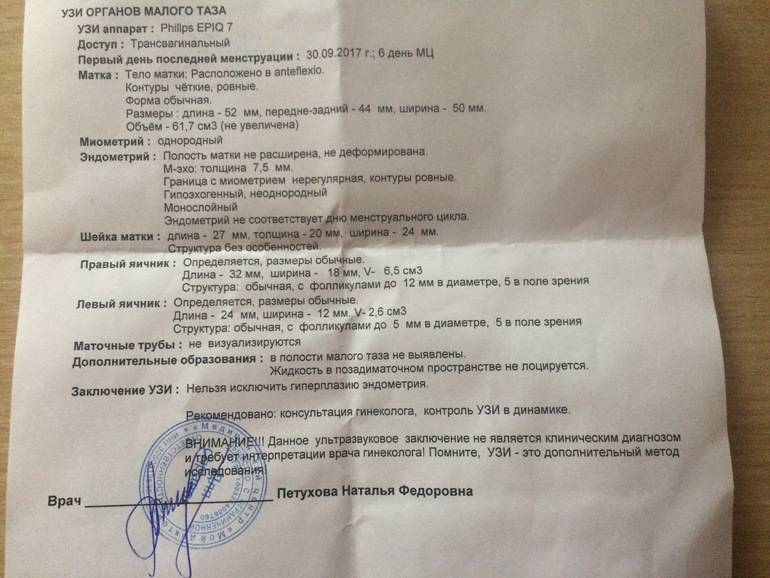

Медицинская диагностика: Гиперплазия эндометрия на УЗИ

Раздел: Мудрость в объективе